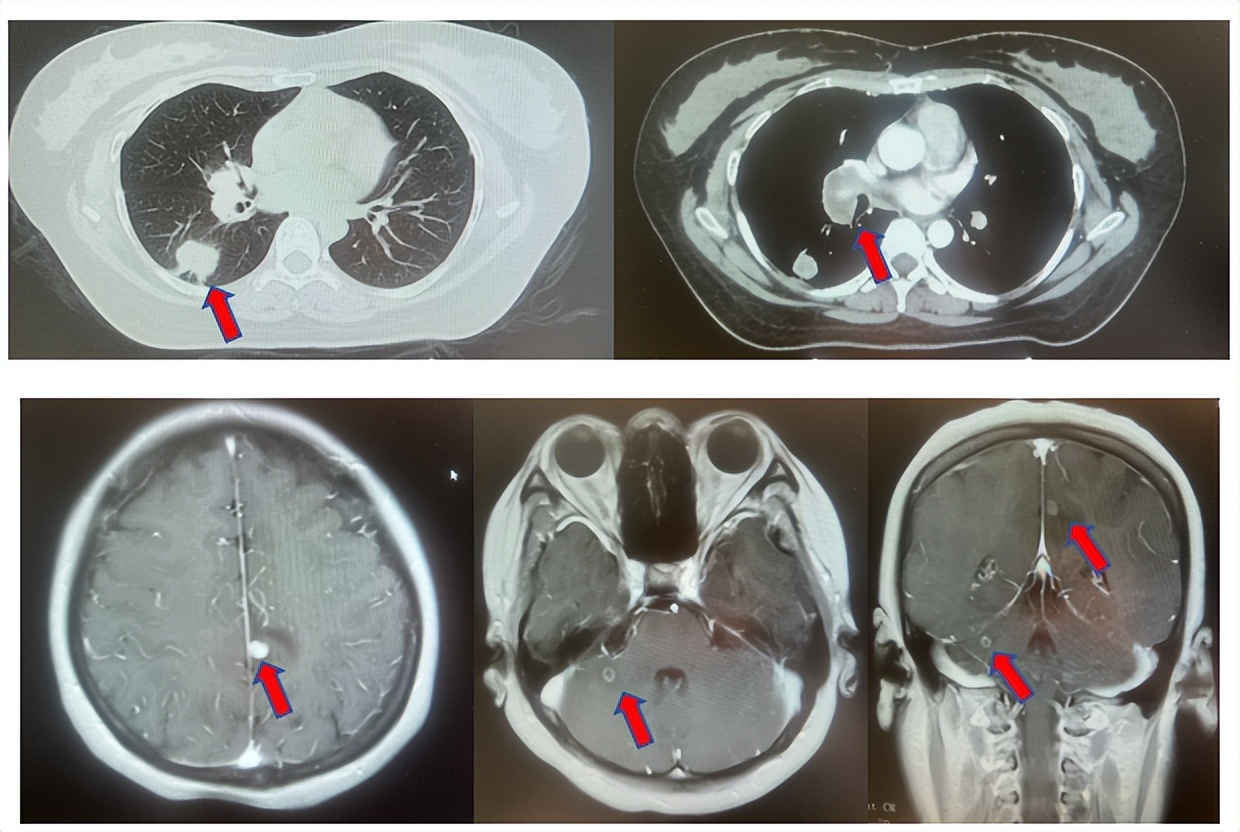

2.2影像学检查(图5)

肺+全腹CT增强:右肺中叶肿块,考虑恶性,双肺胸膜下炎症,双侧胸膜局限性增厚,右侧锁骨上淋巴结增大,纵隔淋巴结稍大;

颈部CT增强:右侧锁骨上及右颈部、纵隔多发淋巴结肿大。

脑MRI增强:头MR平扫+增强未见确切异常。

图5:上两图分别展示基线时肺CT肺窗及纵隔窗右肺中叶病灶影像,下两图表示基线状态时纵隔淋巴结及锁骨上淋巴结影像。

患者符合我科正在开展的一项“评估信迪利单抗或安慰剂联合培美曲塞和铂类化疗用于晚期或复发性肺鳞状细胞非小细胞肺癌一线治疗有效性和安全性的随机,双盲,III期研究(ORIENT-11)”临床研究入组条件,应用信迪利单抗或安慰剂联合培美曲塞+卡铂治疗4周期,信迪利单抗或安慰剂联合培美曲塞维持治疗13周期,后应用信迪利单抗或安慰剂应用至2年。试验结束后出组,揭盲患者为信迪利治疗组。治疗期间最佳疗效肺内病灶近CR(图6)。停药后每3个月-6个月复查随访,未见肿瘤复发转移征象(图6),截止至目前为止,一线无进展生存已超过75个月。

图6:上三图分别展示2019年6月患者达到最佳疗效时肺CT肺窗及纵隔窗右肺中叶病灶及锁骨上淋巴结影像,下两图表示2025年2月患者最近复查评效时肺CT肺窗及纵隔窗肺内病灶影像